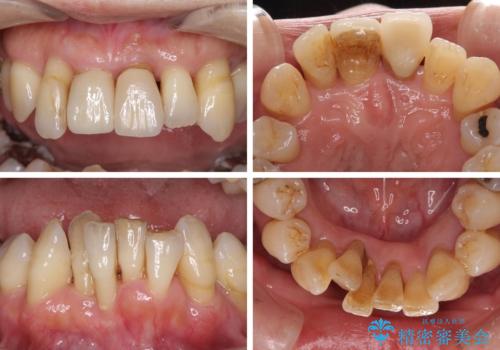

- 近医に通い続けるも、一向に不快感が改善しないとのことで来院された患者様です。

診察を行ったところ、重度歯周病の状態の上に上下の歯列が著しい叢生という状態でした。

歯周初期治療として抜歯や歯槽骨再生治療を行い、さらに歯周ポケット除去を行った後に矯正治療で歯列を整えて行くこととしました。